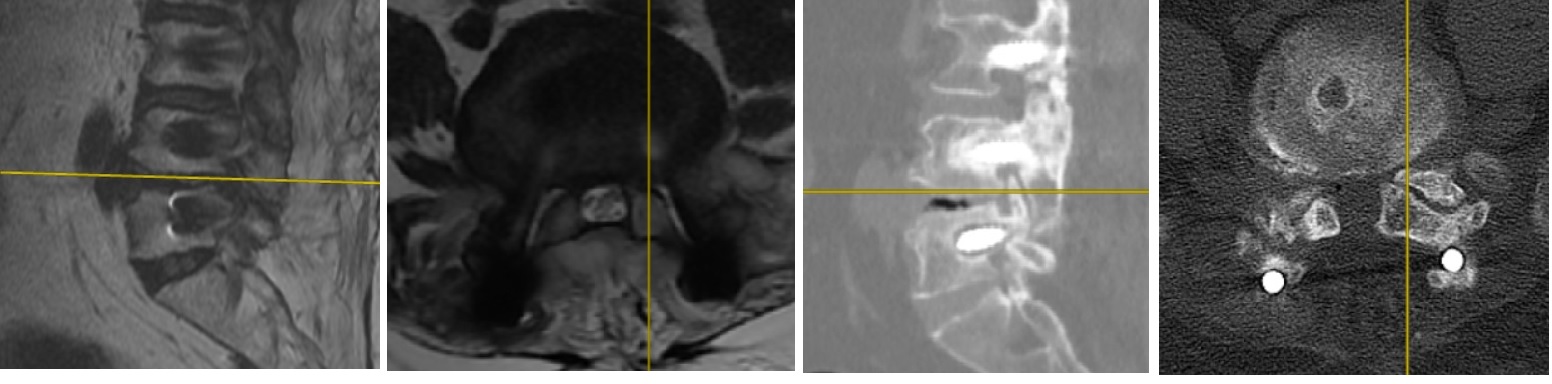

Hastanın beraberinde getirdiği ve bir önceki yıla ait lomber MRG incelemesi aşağıdadır.

2021 Yılı MRG İncelemesi - Lomber Enstrüman Gevşemesi

Resim 1: Bir yıl önce yapılmış olan MRG incelemesinde T11-L5 seviyelerinin stabilize edilmiş olduğu, L2-L4 seviyelerinde laminektomi bulunduğu ve L4-5 seviyesinde kanalda darlık olduğu görüldü. Ayrıca lomber lordozun düzleşmiş olduğu dikkati çekmektedir. MRG kalitesi düşüktür.

Uzun segment (T11-L5) stabilizasyon yapılmış olan hastanın istirahatte bulunan kalça ve bacak ağrıları ve uyuşma yakınmaları spinal kanalda ya da nöral foramenlerde daralmalara bağlı nöral bası düşündürtmektedir (Bacaklardaki kramplar nörojenik kladikasyon tablosunun bir parçası olabilmekle birlikte, tipik siyatalji tablosunun bir parçası değildir, başka sebepler de aramak gerekir).

Hareketle artan bel ağrısı instabilite, alt lomberde implant üzerine basmakla uyandırılan şiddetli ağrı ise implant gevşemesi lehinedir.

Bu hastada olası tanılar komşu segment hastalığı (T11 üstü ve L5 altı seviyelerde hızlanmış dejenerasyona bağlı darlıklar ve/veya instabilite) ve implant gevşemesidir. Stabilize edilmiş L4-5 seviyesinde darlık görülmesi, buna karşın L5-S1 seviyesinin nisbeten korunmuş oluşu L4-5 seviyesinde füzyon oluşmadığı ve implant gevşemesi olabileceği yönünde fikir oluşturmaktadır.